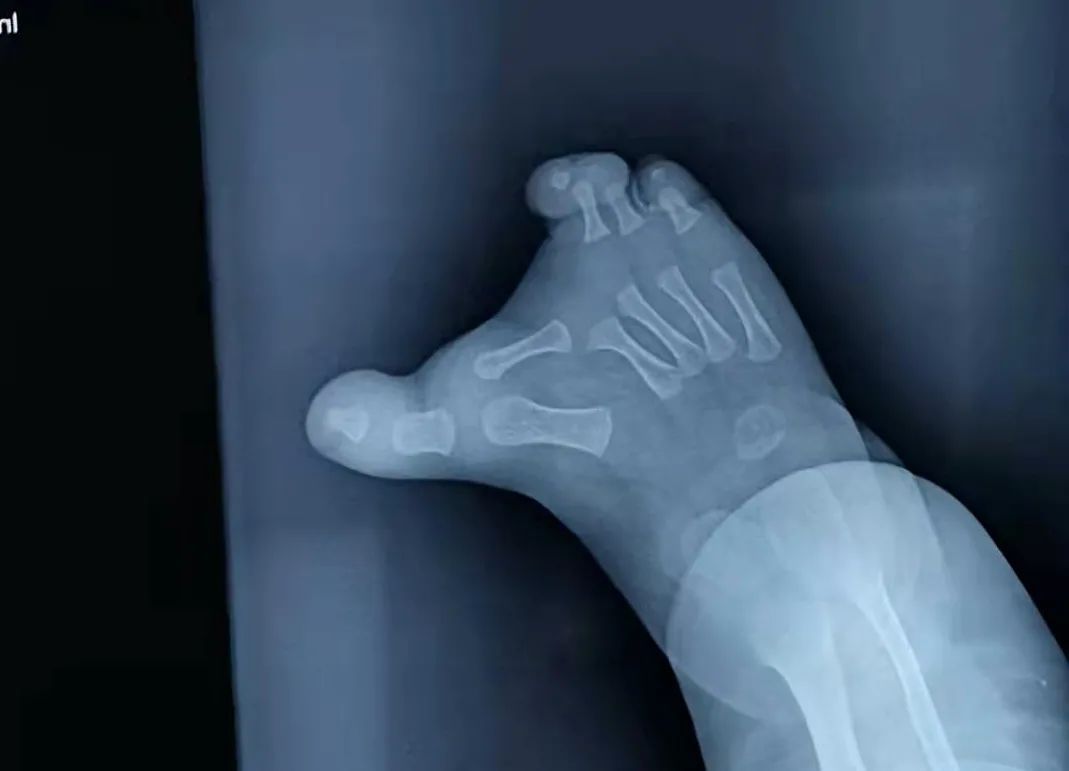

宝宝是双脚并趾,通过X片我们可以看到宝宝的第二趾是横向生长的,这种情况是要尽早治疗的,因为第二趾还在不断地生长中,时间越长,对其他脚趾的影响就越大。

针对第二趾我们有两种治疗方案,一是保留,二是拿掉。因为这第二趾比较长,还没有指甲,保留的话外观上就不是很好看。所以从外观上出发,我建议拿掉第二趾,妈妈也更倾向这一方案。